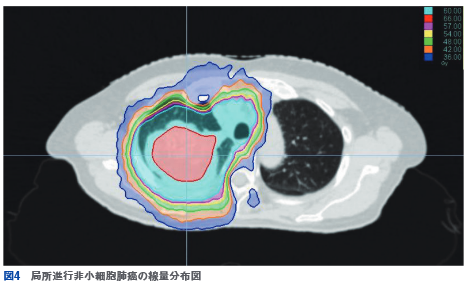

強度変調放射線治療の強度変調のレベルは高い。Radixact導入前は、いわゆるstep and shootにて主に前立腺癌、頭頸部癌が対象であったがRadixact 1台体制中に大半の疾患に拡大し、頭部定位放射線治療、Radixact Synchronyによる追尾照射を導入した。図3に頭部血管肉腫症例の線量分布を示す。頭部から顔面に及ぶ凹凸のある部位においても病変に均一に照射し、繋ぎ目のない線量分布を得ることできた。電子線を使わないことでスループットの向上にも大きく寄与している。なお、当院では菌状息肉症、ケロイドと睾丸に対してリニアックの電子線を使用する予定である。図4に局所進行非小細胞肺癌の症例を示す。脊髄、肺、甲状腺、気管支、食道全てに配慮して線量分布の作成が可能であった。経過観察で無気肺を呈したのは右上葉のみで右中葉は温存でき、晩期有害事象は軽度の食道炎のみであった。全身照射では、肺、腎臓の線量を抑制した上で、全身に均一な照射が可能である。他にも、乳房全切除術後放射線療法ではhalf field法の様な胸鎖関節レベルでの繋ぎ目がなく、内胸リンパ節領域に照射しつつ、肺の線量を抑制可能である。頭部定位放射線治療では、全脳照射との併用を容易に施行可能である。2台体制に復帰した後も、高精度放射線治療はRadixact主体に行われている。